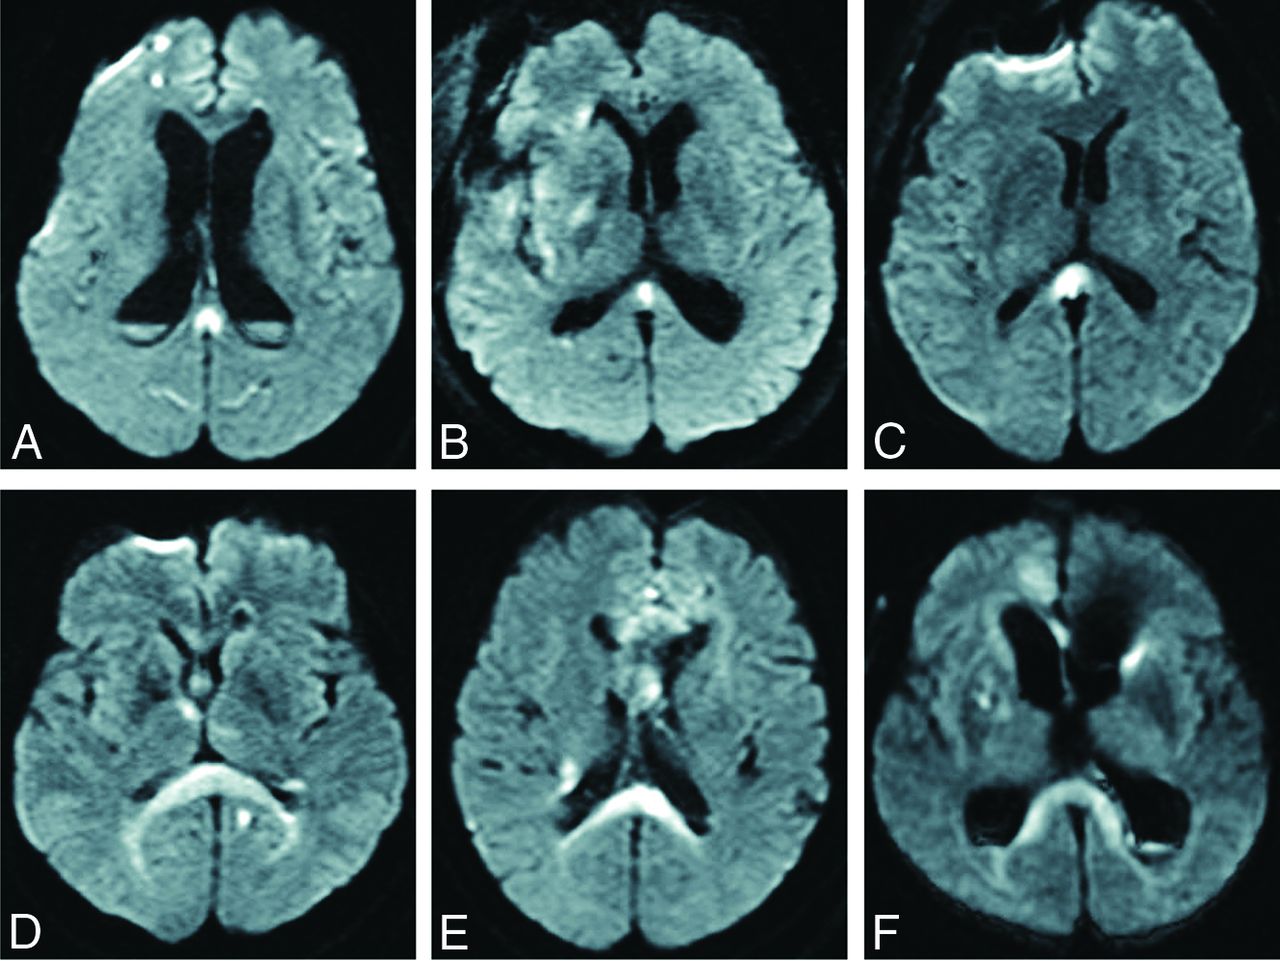

Of the 286 cases of aneurysmal SAH, we excluded 12 cases that could not be evaluated due to early death, 10 cases that showed SAH of unknown origin, and 5 cases in which only external ventricular drainage was performed. The remaining 259 patients underwent curative treatment (clipping or coiling) and MR imaging multiple times, and we analyzed these cases. Of the 259 cases, DWI detected CLOCC in 33 patients (12.7%). These patients comprised 5 men and 28 women, with a mean age of 68.6 years (range, 40–94 years). In 33 cases with CLOCC, the mean period from the onset of SAH to detection of CLOCC was 6.3 days (range, 0–25 days). MR imaging showed CLOCC in 4 cases on day zero, 21 cases within days 1–7, five cases within days 8–14, and 3 cases on or after day 15. CLOCC were detected after clipping or coiling in 25 cases (75.8%) and before clipping or coiling in 8 cases (24.2%). CLOCC resolved in all cases, and the mean period from onset of SAH to the disappearance of CLOCC was 35.7 days (range, 9–78 days). On DWI, CLOCC were classified as the small type localized to the splenium (mean maximum diameter, 10.4 mm) or the large type extending along the ventricle (Fig 1). Among all 33 patients with CLOCC, 26 patients (78.9%) showed the small type and 7 cases (21.2%) showed the large type. CLOCC were identified as asymmetric in 16 of the 33 patients.

Two types of CLOCC: a small type localized to the splenium (A–C) and a large type spreading along the ventricle (D–F).